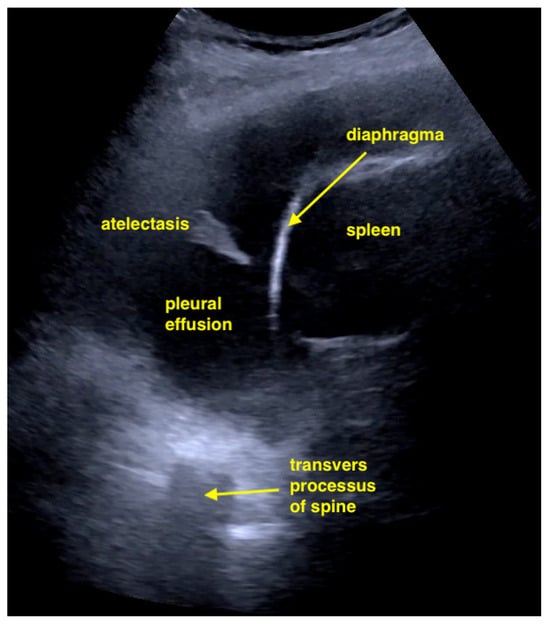

Pleural effusion evaluation can be performed with either a sector or convex probe in the costophrenic angle on both sides of the thorax. Estimating the general size of an effusion (small versus large) is easy, however, obtaining a relatively precise volume estimate is difficult, with multiple different formulas available. Much more important is to realize whether an effusion is present [] (Figure 4).

Figure 4.

Large pleural effusion with compression atelectasis. If there is uncertainty as to whether it is a pleural effusion or not, the spine sign is shown. The transverse processes above the diaphragm are only visible if there is fluid in the pleural space. Otherwise, they are erased by lungs containing air.